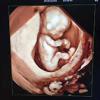

今天佛山都市妇产医院就来和孕妈们说说孕期超声检查的那些事吧~...

准妈妈孕期必做的检查,以免错过最佳时间。 在怀孕期间, 为了确保胎儿的健康发育, 只能通过产检的方......